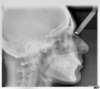

Décalage traité par gouttières

Fin de traitement